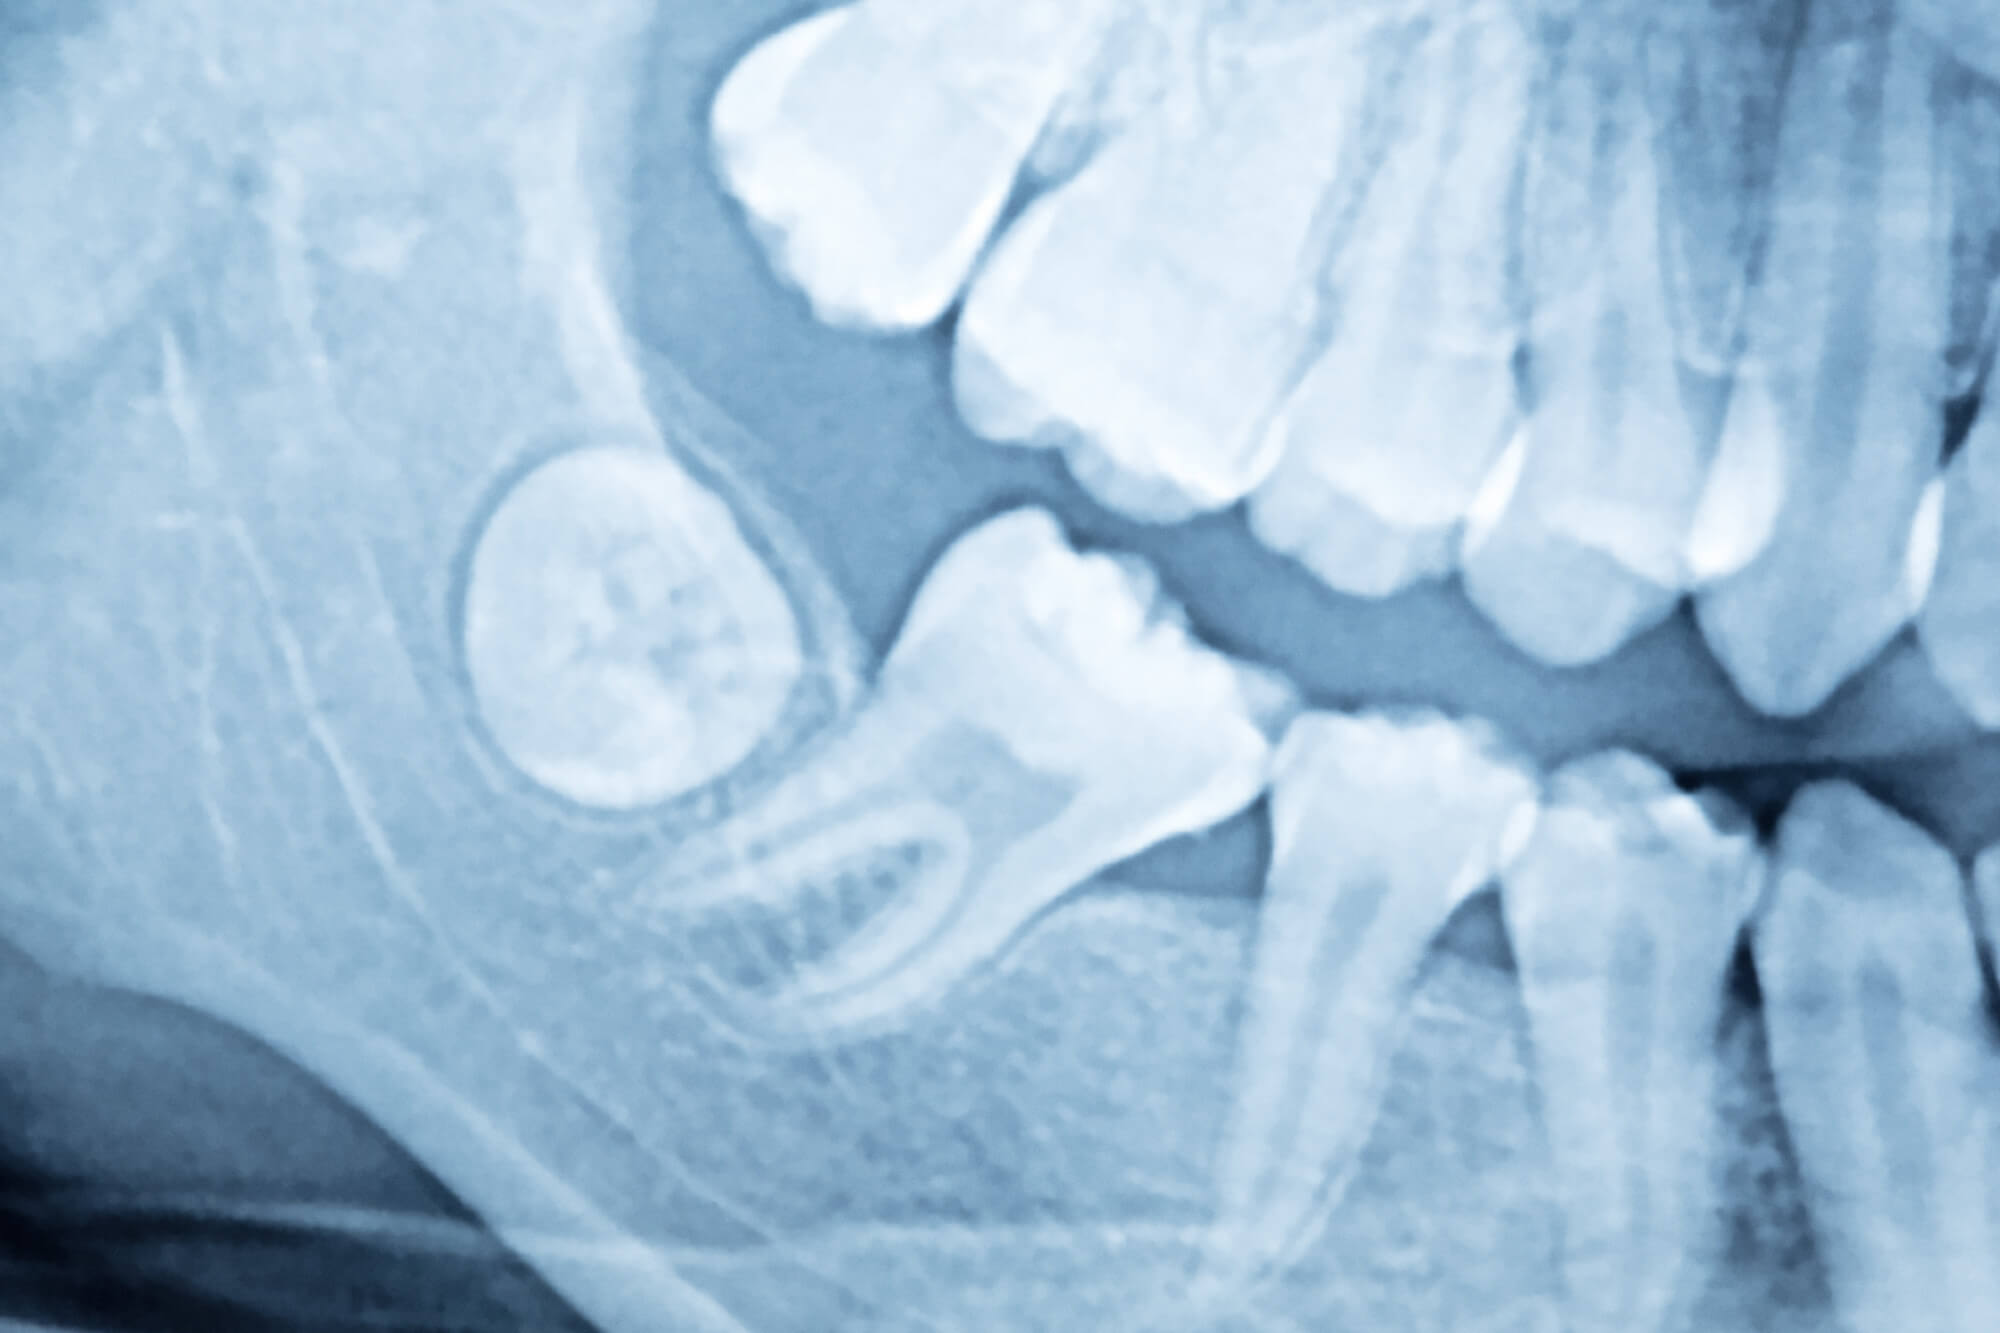

A bölcsességfoggal összefüggő problémák megelőzéséhez érdemes 14 éves korban panorámaröntgent készíttetni, amelyen már kivehetőek a bölcsességfogak csírái. Ennek alapján a fogorvos meg tudja mondani, hogy az előtöréskor lehet-e számítani valamilyen nehézségre. Amennyiben a válasz igen, javasolni fogja a bölcsességfog(ak) eltávolítását, mivel ebben a korban a beavatkozás sokkal kevesebb kellemetlenséggel jár.

Legyen szó akár foghúzásról vagy műtéti eljárásról, a beavatkozás előtt szájüregi vizsgálatra és röntgenfelvételekre is szükség lesz. Az alsó bölcsességfog szájsebészeti feltárása előtt fogászati CT-felvételre is sor kerülhet, mert az alsó fogak túl közel lehetnek az alsó állkapcsot és alsó ajkat érintő idegekhez, ami nagyban befolyásolhatja az eljárás menetét. A felső bölcsességfogak eltávolítása azonban többnyire egy sima foghúzással megoldható, főként, ha a fog teljesen előtört. Gyulladt bölcsességfog esetén a fogorvos gyulladásgátló szereket vagy antibiotikumot is felírhat, hogy visszaszorítsa a fertőzést a beavatkozás előtt.

Fogászatunk saját röntgen- és CT-laborral rendelkezik, így az egyszerű kisfelvételtől a panorámaröntgenen át a 3 dimenziós CT-ig minden szükséges felvételt elkészítünk a precíz diagnózishoz.